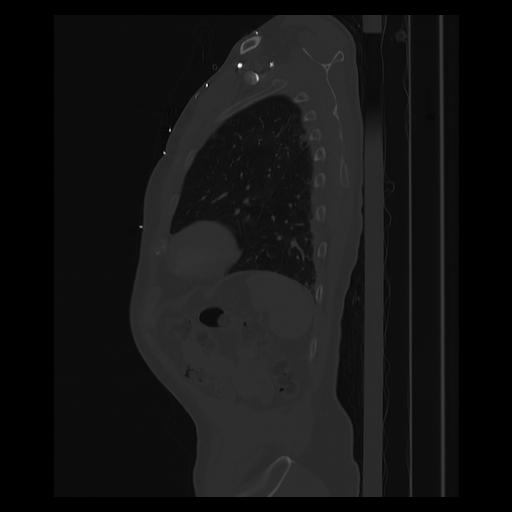

33 PULMON,CE,Sagittal,3.000,PULMON,Sagittal,